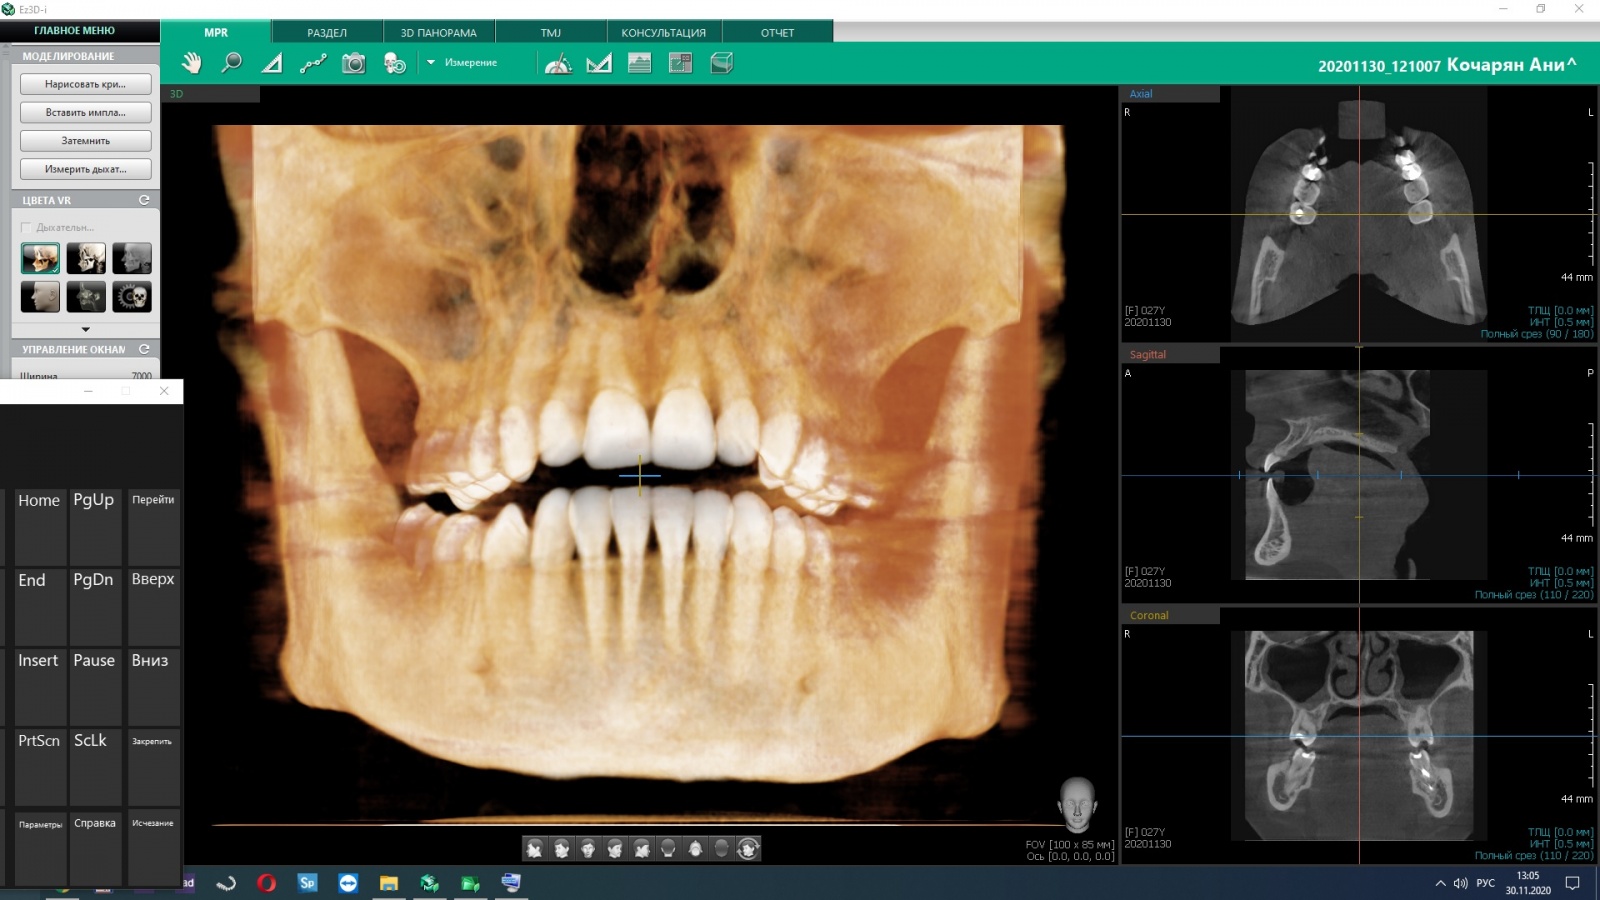

Диагностика

КТ высокого разрешения — понятно.

image

Важно делать быстро. Вот я прямо в кабинете получаю к ней доступ, пока пациент лежит:

К слову, у нас нет бумажных снимков, но есть негатоскопы (просмотровые столы). Потому что таковы требования нормативов.

По статистике США, 80 % кариесов можно было бы диагностировать раньше. Поэтому у нас, например, так:

• Прицельные внутриротовые снимки.

• Прицельные интерпроксимальные снимки.

• Компьютерная томография.

• Инструментальные методы обследования.

Если вас пугают снимки в плане лучевой нагрузки, то сразу скажу, что она по сумме снимков примерно в 80–150 раз меньше одного прохода того панорамного сканера, куда вы пихали голову в кабинете у зубного врача в любой средней клинике. Потому что технологии.

Интерпроксимальные снимки, где на один снимок помещается сразу восемь контактных поверхностей, делают редко, а они важные, потому что видно кариес самый-самый маленький. КТ помогает увидеть все зубы в объёме, в повороте, видно все воспаления. Телерентгенограмму делают в основном ортодонты или при сложном ортопедическом лечении. Это специальное исследование для проведения антропометрических исследований, то есть оно даёт снимок головы один к одному, и можно проводить угловые измерения величины. Фотопротокол важен для сравнений до и после, потому что это важно и пациенту, и врачу для обучения. Если фотопротокола нет, то через несколько лет будет сложно восстановить картину.